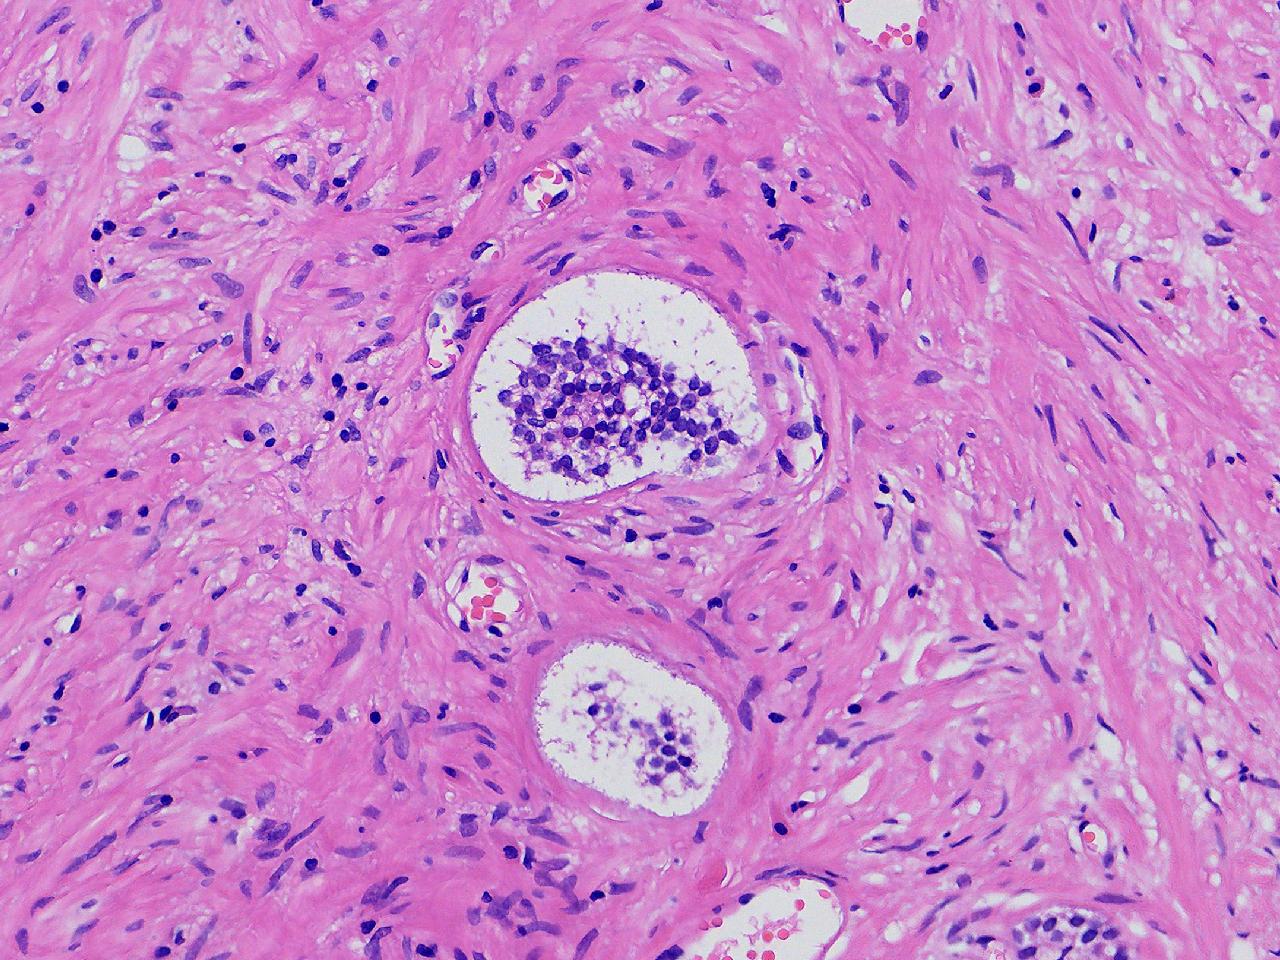

男,68岁,前列腺电切标本。

前列腺电切标本

灰粉色条索状软组织多块,5X4X3厘米。

前列腺增生。

BPH.